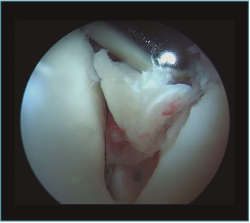

Figura 2. Visión artroscópica desde el portal anteromedial de un osteofito en la coronoides, disecado con un vaporizador de gancho, previamente a su resección con fresa motorizada.

Trabajaremos la parte ósea en primer lugar, resecando los osteofitos de la coronoides y de la fosa coronoidea, así como de la cabeza radial o de la articulación radiocubital si fuera necesario. Una vez hemos finalizado la parte ósea, procederemos realizar la capsulotomía anterior si está indicada.